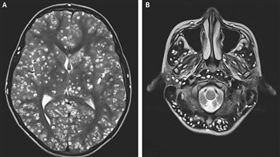

噁爆蟲卵入侵!男寄生蟲遍布大腦喪命

印度一名18歲少年日前因癲癇發作,被緊急送往醫院急診...